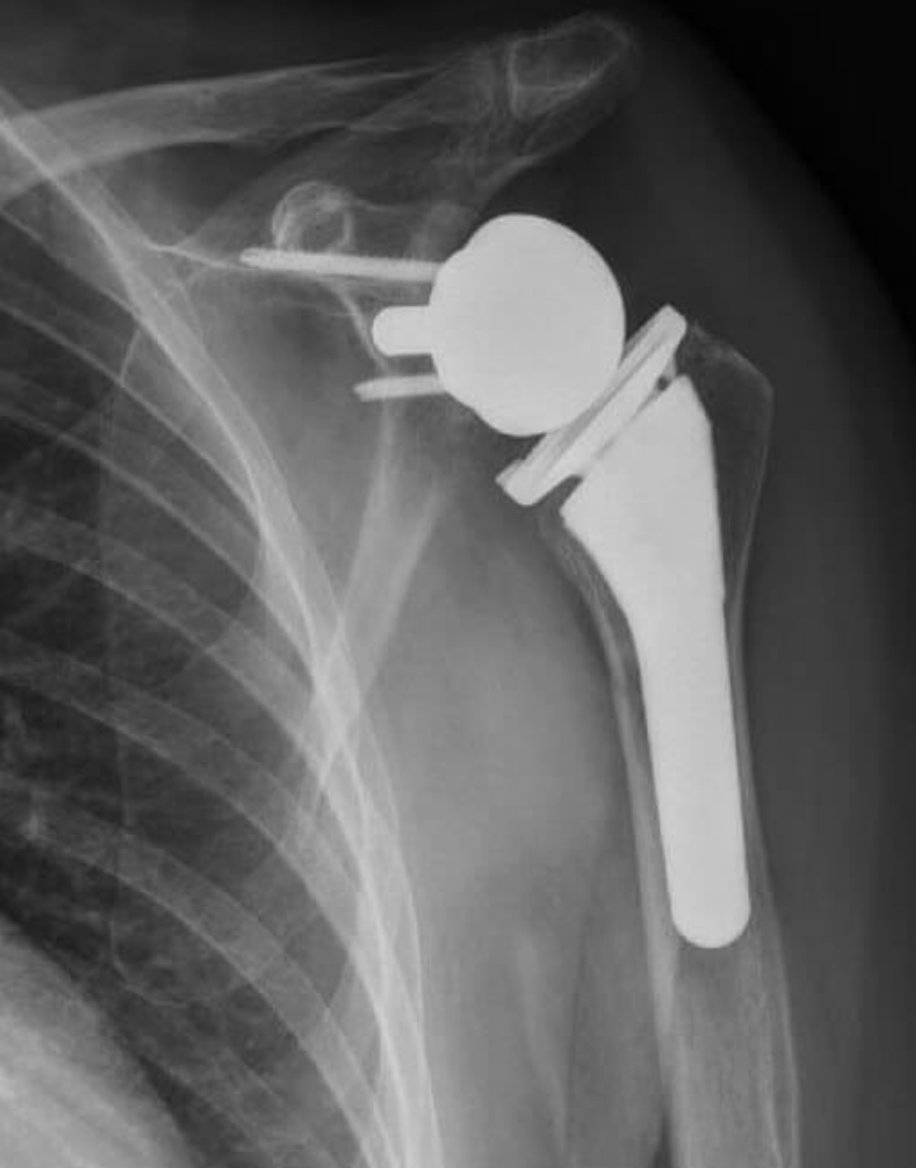

- In RTSA, the normal ball-and-socket structure is switched: the ball is placed on the shoulder blade, and the socket is placed on the upper arm bone.[3][4][5]

- RTSA does not rely on the rotator cuff for movement. Instead, the deltoid muscle (on the outside of your shoulder) helps lift your arm.[1][2][13][10][3][4][11]

X-ray image of a shoulder with a reverse shoulder prosthesis

X-ray image showing a shoulder with a reverse total shoulder arthroplasty

X-ray image of a right shoulder with reverse shoulder arthroplasty